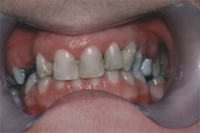

With improvements in materials, particularly with premium, natural looking denture teeth, we are able to create an esthetic restoration that can look completely natural. In many cases of severe break down and malformed, rotated, discolored teeth, the most aesthetic solution can be a denture. Not all dentures are created equally. Depending upon the materials used, the quality of the teeth chosen and the skill of both the dentist and the laboratory technician, the result can have many different appearances. Injection molding of the pink denture base material is much more accurate than the traditional way that most Dentures are made. There is less shrinkage and a better fit.

Dentures should look natural and unnoticeable from natural teeth.

Can you tell if it is a denture?